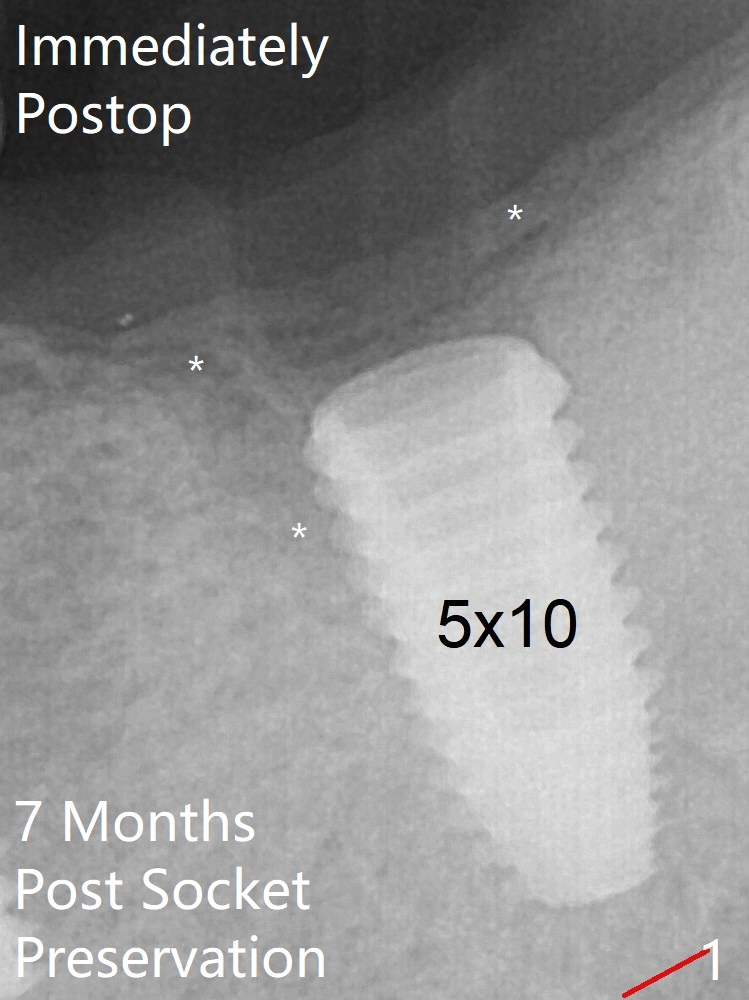

The upper portion of the socket has normal trabecular patterns 7 months post socket preservation (Fig.1, as compared to Fig.4 (immediately post socket preservation)).  The bone density of the upper portion of the previous socket increases 4.5 months post implant placement (Fig.2 *).